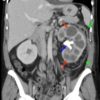

Viêm thận bể thận

» Thông tin: Nữ giới – 51 tuổi.

» Lâm sàng: Đau thắt lưng + Sốt.